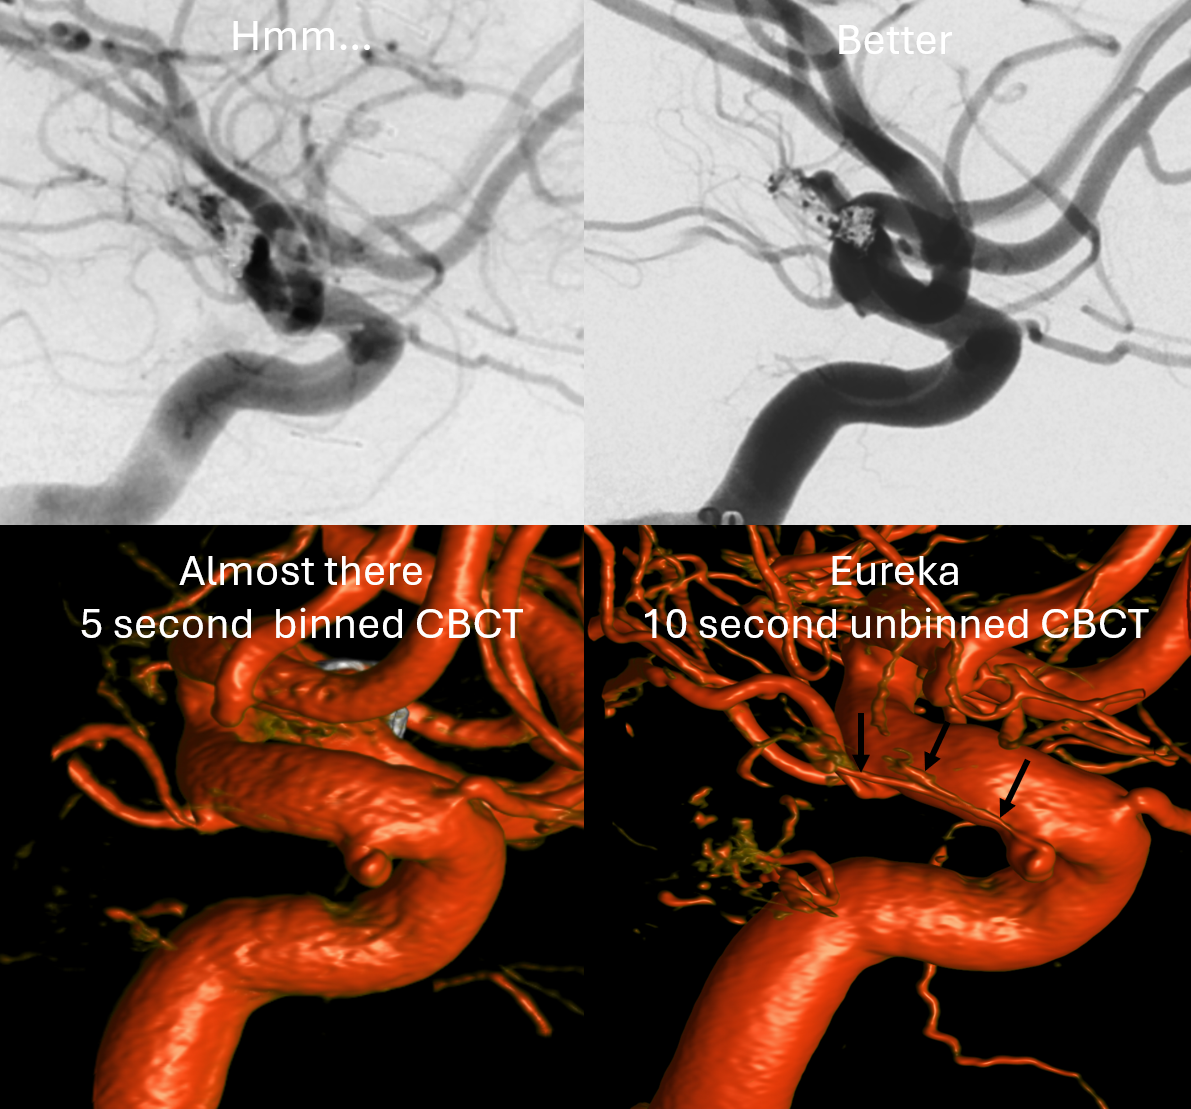

If you want to see hypophyseal arteries, do some high res DYNA of VASO imaging. Because of superimposition over the carotid in lateral views, again, its hard to see. Below is an example of why this artery, always there (always, yes! — occlusion is pathologic always such as athero) depends on technique

Stereos and MIPs. Both superior and inferior hypophyseals are well seen. The superior hypophyseal, despite being invisible on standard issue views, is quite large, even having two branches to the hypophysis.